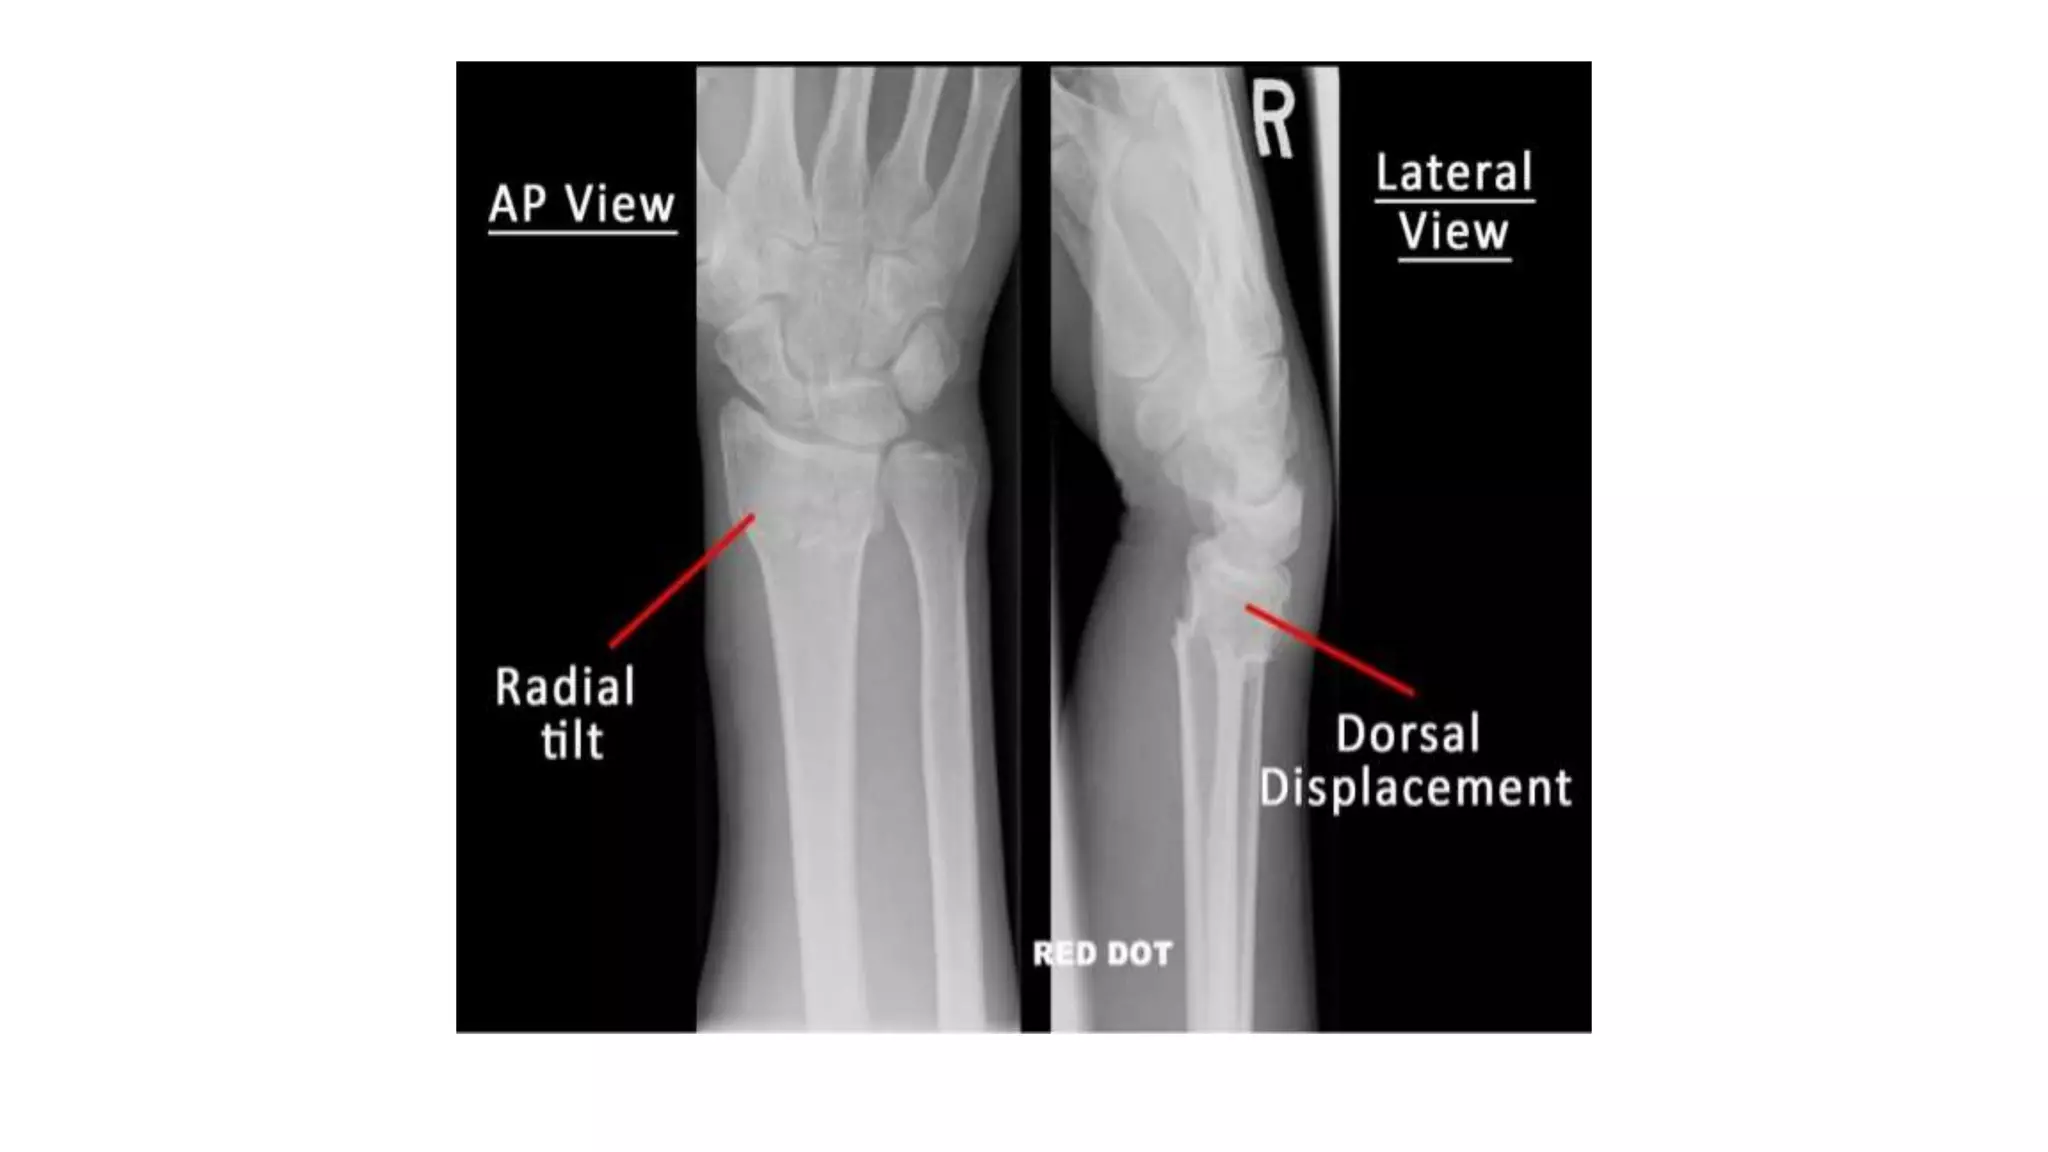

- X-ray shows there is a transverse # of the radius @

the cortico-cancellous junction.

- & often the ulnar styloid process is broken off.

- The radial fragment is impacted into radius & backward tilt.

 Force is applied in the length of the forearm with the wrist in

extension.

 The bone fractures at the cortico-cancellous junction & the distal

fragment collapses into extension, dorsal displacement, radial tilt and

shortening.